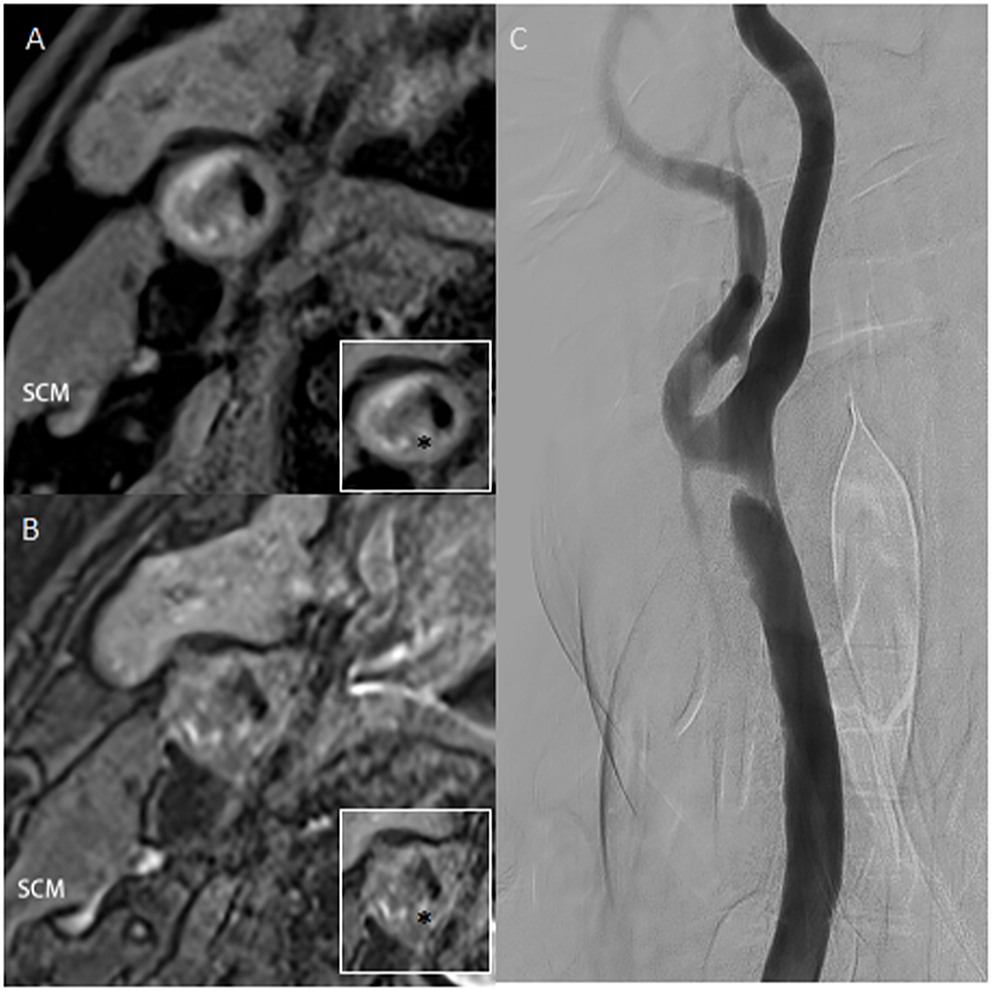

Figure 1

(A,B) High-resolution T1 and T2 weighted images of plaque. The ratio of the highest signal intensity of carotid plaque to sternocleidomastoid muscle was more than 2.0. (C) Digital subtraction angiography confirms an irregular filling defect. Asterisk indicates the plaque component. SCM, sternocleidomastoid muscle.